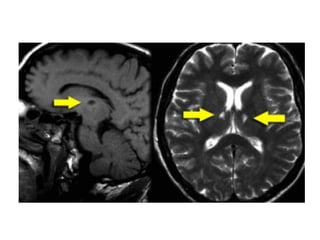

Thrombosis of deep cerebral veins

-The clinical presentation of thrombosis of the

deep cerebral venous system are severe

dysfunction of the diencephalon reflected by

coma and disturbances of eye movements and

pupillary reflexes , usually this results in a

poor outcome

-However , partial syndromes without a decrease in

the level of consciousness or brainstem signs

exist which may lead to initial misdiagnoses

-Deep cerebral venous system thrombosis is an

underdiagnosed condition when symptoms are

mild and should be suspected if the patient is a

young woman , if the lesions are within the basal

ganglia or thalamus and especially if they are

bilateral

Patient with deep cerebral vein thrombosis , notice the bilateral infarctions in

the basal ganglia

The same patient , there is absence of flow void in the internal

cerebral veins, straight sinus and right transverse sinus (blue

arrows) , on the MRA the right transverse sinus is not visualized